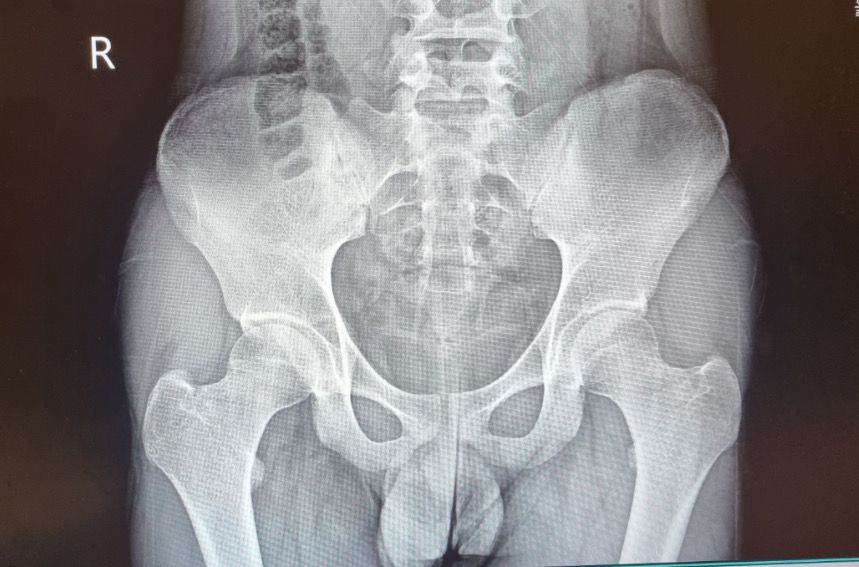

골연령이 만으로 몇세정도인가요??

골연령이 만으로 몇세정도인가요?

• 1번 째 사진

엑스레이 사진 한장으로는 정확한 골 연령의 평가가 어려울 뿐더러 정확한 수치는 개인마다 차이가 있고, 일반적인 기준은 따로 없습니다.

보통 일반적으로 청소년기에는 골연령이 만 나이보다 더 낮거나 높을 수 있고 이는 성장 속도에 따라 개인마다 차이가 있습니다. 정확한 평가를 원하신다면 전문의의 진료를 받아 보시는 것도 좋을 것으로 생각됩니다.

골반의 장골능의 선이 다 이어진 것을 성장이 종료되었다고 보는데요, 아직 완전히 이어진 것이 아니기 때문에 성장기가 끝나지 않았다고 유추해볼 수 있겠습니다.

정확한 골연령의 측정은 검사장비가 갖춰진 의료기관에서 시행하시는 것이 정확하고, 올려주신 엑스레이 사진으로 판단하기에는 경과관찰이 필요하기 때문에 올려주신 사진 한장으로 단적으로 판단하기에는 한계가 있습니다.